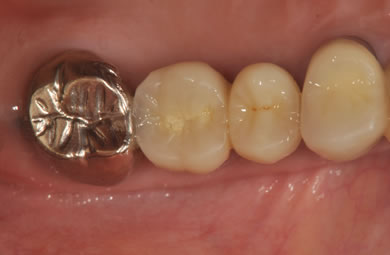

インプラントの症例写真 IMPLANT

スピードインプラント治療+セラミック治療

| 治療内容 | インプラント3本(抜歯即日スピードインプラント)、ハイブリッドセラミック5本 | ||||||||||||||||||||||||||||||||

| 総治療費 | 1,399,819円 | ||||||||||||||||||||||||||||||||

| 治療期間 | 8ヶ月 |